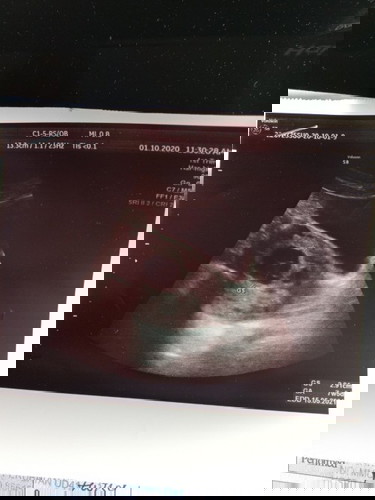

Hye all Mom boleh bagi pencerahan tentang hasil scan saya yg berjarak 9 hari ini

Jarak scan 9hari Tadi dokter kata kena cuci pasal baby nampak tak berkembang Sbelum nya saya pernah kongsikan hasil scan pertama dokter kata kantung kosong N hari ini saya kongsikan karna sy ingin dengar pendapat dr all mom yg lain jika ada yg pernah mengalami hal sama atau pon bnyk sedikit sy minta nasehat dari all mom tq 🙂